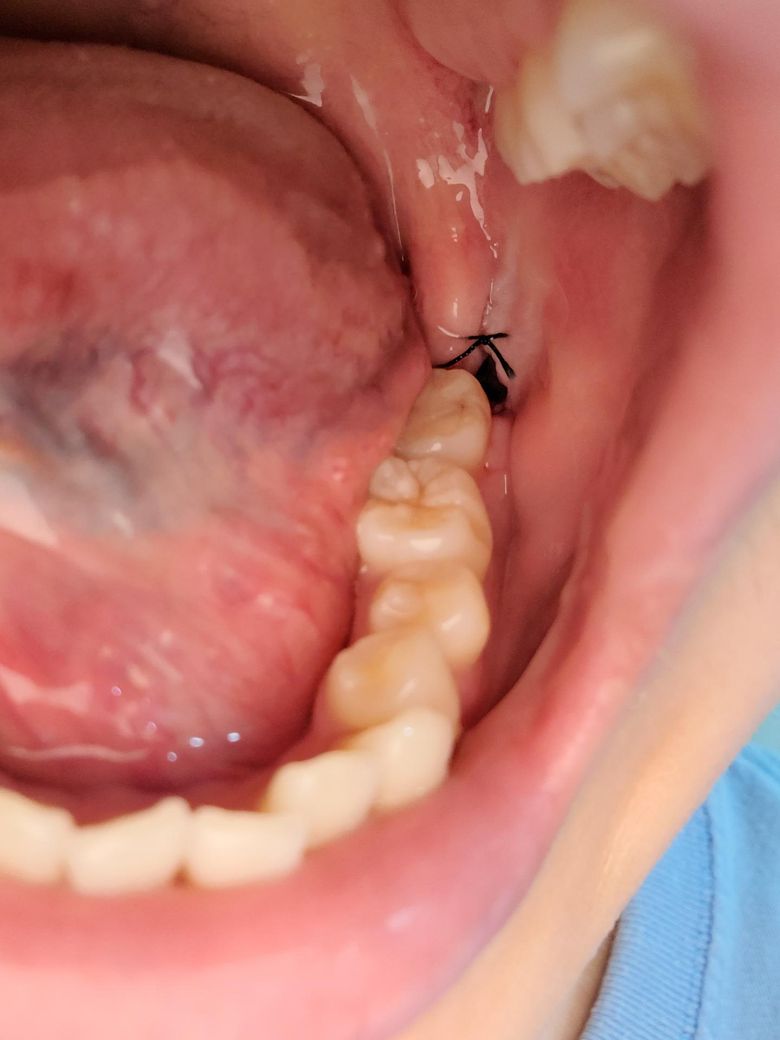

매복사랑니 발치 후3일차 저부위에 구멍생기는게맞나요

음식물찌꺼기인지 하얀색이껴있길래 입 행구기도해보고 제거해보니 구멍이 생기는데 원래 이러는건가요 아니면 치과를 가봐야하는 정도인가요? 아프거나 그러지는않은데... 네이버에쳐보니 제거하지말라고하던데 이미했으면 어떡해요....

앞으로는 건드리지않으면 괜찮아질까요 화요일점심전에 발치하고 다음주수요일 9시30분쯤 실밥제거하러가요. 많은답변부탁드려요ㅠㅠ

발치한곳 잇몸이 다 아물지 않아서 그러는 겁니다. 큰 문제가 잇는건 아니니 걱정하지 않으셔도 됩니다.

음식물 찌꺼기등 이물질은 제거해주는 것이 맞으나 발치 후 잇몸 회복을 위한 염증,육아조직은 그대로 두어야 합니다

발치 후 3일차에 구멍이 있는것은 정상입니다